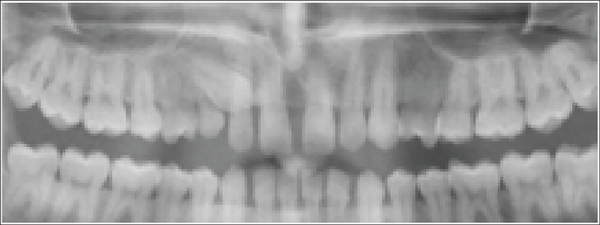

Step 1: The OPGs were uploaded in JPEG/TIFF format and cropped using a bounding box of uniform size of 80 × 215 pixels (Figures 2 and 3).

Point for Cropping Orthopantomogram.

Cropped Image of Orthopantomogram.